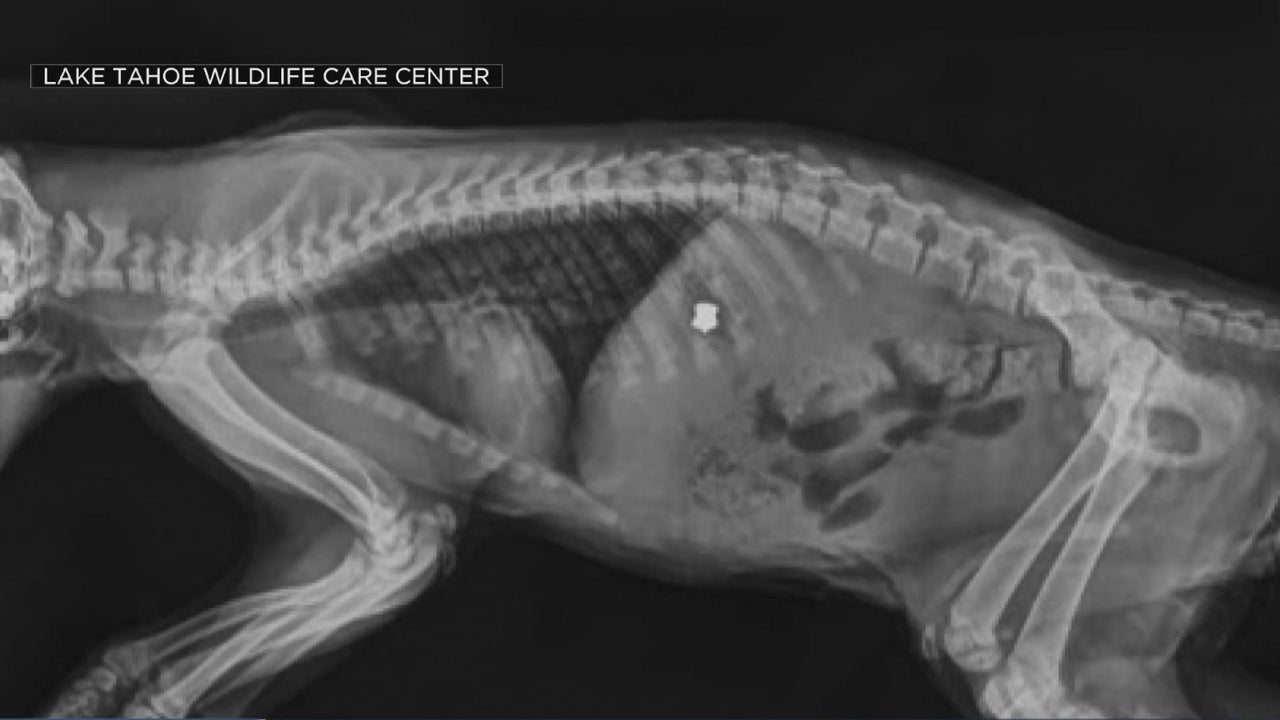

More Animals In Tahoe Area Are Being Shot With BB Guns, Causing Paralysis

X-rays show the damage the pellets are causing as animals big and small have been impacted with some even being paralyzed.